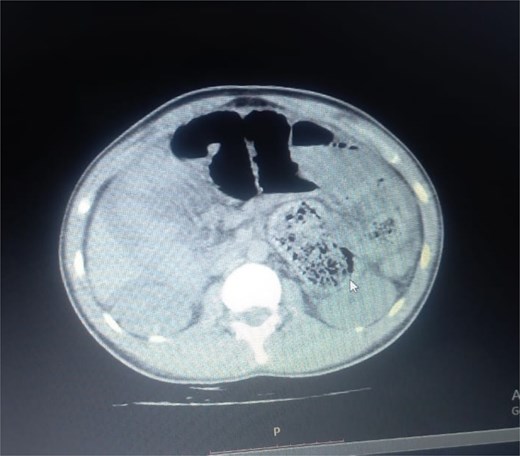

Initial radiographic evaluation with a plain abdominal X-ray confirmed the clinical suspicion of acute intestinal obstruction, demonstrating multiple air-fluid levels and diffuse small bowel dilatation (Fig. 1). To further delineate the underlying etiology, a contrast-enhanced computed tomography (CECT) scan was performed; providing critical diagnostic information it revealed, in the right iliac fossa, a striking encapsulation of the small intestine loops within a sac-like membrane, accompanied by ascites. This constellation of findings formed a pathognomonic cocoon-like structure (Fig. 2). Furthermore, the CECT identified a concurrent gut malrotation, evidenced by a left-sided displacement of the colon (Fig. 3). Laboratory findings showed an elevated total leukocyte count (TLC) of 21 000, indicative of inflammation, while other parameters were within normal limits. The patient underwent an exploratory laparotomy. Intraoperatively, the abdominal viscera were encased within a thick fibrous membrane (Fig. 4), containing ascitic fluid. The membrane was incised, adhesiolysis was performed, and the entrapped small bowel loops were released, and then a kink in the small intestine causing obstruction was identified and corrected. Additionally, the appendix was found to be secondarily involved in the encapsulating process. It was encased in the dense fibrocollagenous membrane, forming an inflammatory mass consistent with chronic serositis and localized fibrosis, rather than a classic acute appendicular phlegmon. Based on this intraoperative assessment that the mass was a manifestation of the cocoon’s chronic inflammation, a simple appendectomy was performed instead of a more extensive right hemicolectomy. This procedure was necessary to achieve complete release of the entrapped bowel, remove this localized inflammatory focus, and obtain a specimen for histopathology to definitively rule out a primary appendiceal pathology as a secondary cause of the peritonitis. Furthermore, ascitic fluid analysis showed no bacterial or mycobacterial growth, ruling out tuberculosis and the histopathological examination confirmed the fibrocollagenous nature of the membrane. The patient recovered well postoperatively and was discharged on the sixth day with advice for a follow-up after 2 weeks. At the follow-up visit, he reported no symptoms, and abdominal imaging confirmed the absence of obstruction. Histology further confirmed the benign fibrous nature of the membrane, with no signs of malignancy.

Abnormal positioning of encapsulated small bowel. This axial CT view, taken at a lower abdominal level, illustrates the profound anatomical derangement. The entire cluster of small bowel loops is seen encased and displaced into the right iliac fossa, a finding consistent with the combined effects of the cocoon membrane and the patient’s gut malrotation.